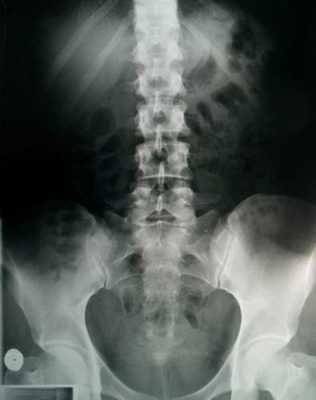

После опроса о симптомах и осмотра врач направляет пациента на рентген, УЗИ, КТ, МРТ или общий и биохимический анализ крови. Процедуры необходимы для того, чтобы определить масштаб проблемы. Также на основе их результатов врач устанавливает причину защемления седалищного нерва и обнаруживает воспаления.

Для постановки очага заболевания необходима диагностика. Она включает в себя несколько процедур:

- Рентгенографию

Рентгеновские снимки позволяют увидеть фактическое состояние позвонков и межпозвоночных дисков, снимки следует делать минимум в двух проекциях стоя и лежа.

Диагностикой ишиаса занимается врач-невропатолог. Он записывает жалобы, проводит осмотр пациента, тесты на синдромы посадки, Сикара и Легаса. Назначает аппаратную диагностику, чтобы исключить другие заболевания со схожей симптоматикой, например, болезнь Бехтерева, спондилит или миеломную болезнь. В числе рекомендованных аппаратных обследований — рентген, МРТ и КТ.